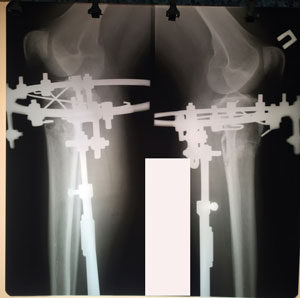

Дата операции - 15.07.2019г.

Дата снятия аппаратов - 15.10.2019г.

Срок сращения 90 дней.